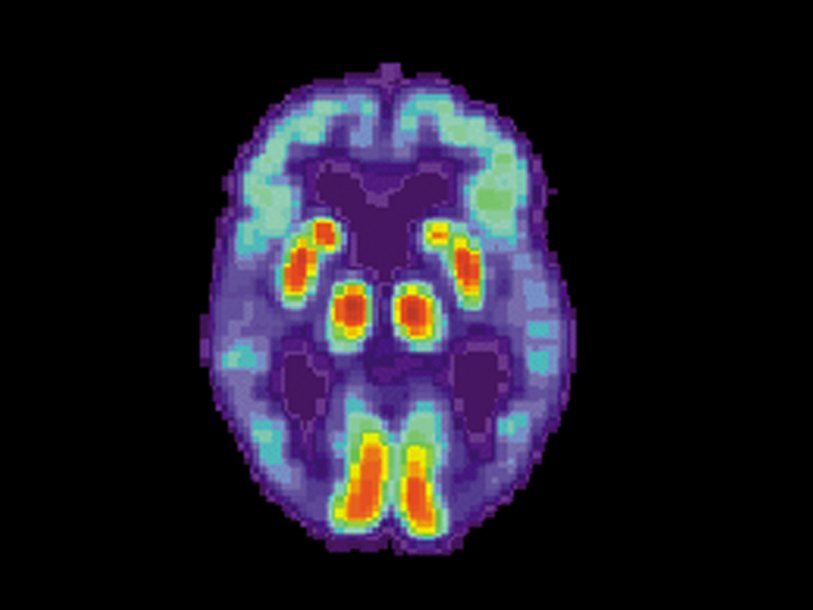

При помощи позитронно-эмиссионной томографии учёные определяли, в каких участках мозга распространяется тау-белок. Исследователи говорят, что карты его распространения у мужчин и женщин различаются, при этом подтверждается гипотеза о более быстром его распространении в мозге женщин.